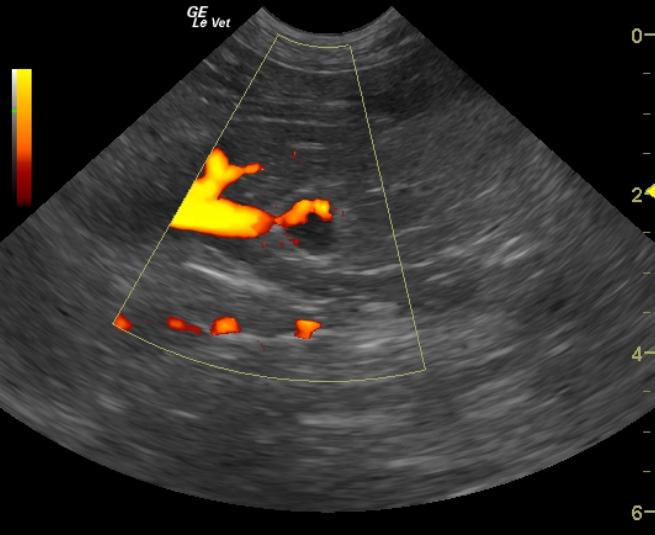

A 13-year-old FS DLH cat was presented to the clinic for the evaluation of a swollen abdomen, alopecia, and anorexia. The cat had a prior history of surgical correction of a corneal ulcer. The blood chemistry performed at the time of the corneal ulcer had shown a mild azotemia and hyperamylasemia. The CBC showed a low HCT, neutrophilia, and lymphopenia. The T4 was within normal limits. The urinalysis showed a pH within normal limits and a low specific gravity (1.013.) The urine had a clear, yellow appearance, but there was proteinuria (1+) and hematuria (3+) on the dipstick.

A 13-year-old FS DLH cat was presented to the clinic for the evaluation of a swollen abdomen, alopecia, and anorexia. The cat had a prior history of surgical correction of a corneal ulcer. The blood chemistry performed at the time of the corneal ulcer had shown a mild azotemia and hyperamylasemia. The CBC showed a low HCT, neutrophilia, and lymphopenia. The T4 was within normal limits. The urinalysis showed a pH within normal limits and a low specific gravity (1.013.) The urine had a clear, yellow appearance, but there was proteinuria (1+) and hematuria (3+) on the dipstick. The sediment confirmed hematuria with a RBC count of 4-10/HPF. Microalbuminuria was present. Repeat bloodwork revealed a marked azotemia, severely elevated creatinine, as well as hyperkalemia, hypermagnesemia, hyperamylasemia, and an elevated CPK. The CBC showed a thrombocytopenia and lymphopenia.